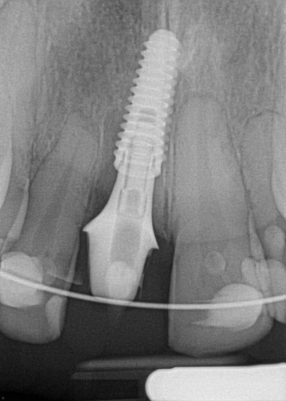

Figure 6 and Figure 7 depict a mature smile with many implant restorations. An analog impression was sent to the laboratory. The impression was scanned by the laboratory, a model was created virtually, and the implant dimensions and position were defined. The 3D surgical guide was fabricated (Figure 8), allowing the patient to receive his therapy swiftly and predictably. Tooth No. 8 was extracted, and the implant was placed and immediately loaded with an acrylic provisional treatment crown (Figure 9). The screw-retained treatment crown was fabricated in-office from a previously completed diagnostic wax-up.

After 4 months of healing and integration of the bone around the implant, the digital workflow was initiated to develop the abutment and treatment plan. Another analog impression was made with an impression post and polyvinyl impression. The laboratory scanned the impression and digitized it to create the emergence profile of the milled titanium abutment and the final restoration (Figure 10 and Figure 11). The patient had a considerably thick soft-tissue profile, allowing a milled titanium abutment. The decision to use a titanium abutment was based on the patient's occlusion and propensity to fracture teeth or restorations. The virtual model was gray because the scanner does not recognize the color of the analog impression. The virtual final abutment and crown were approved and fabrication completed. The final restoration met the patient's esthetic values and his ability to function (Figure 12 and Figure 13).

Fig 16. Preoperative periapical radiograph on the day of surgery.

Figure 16